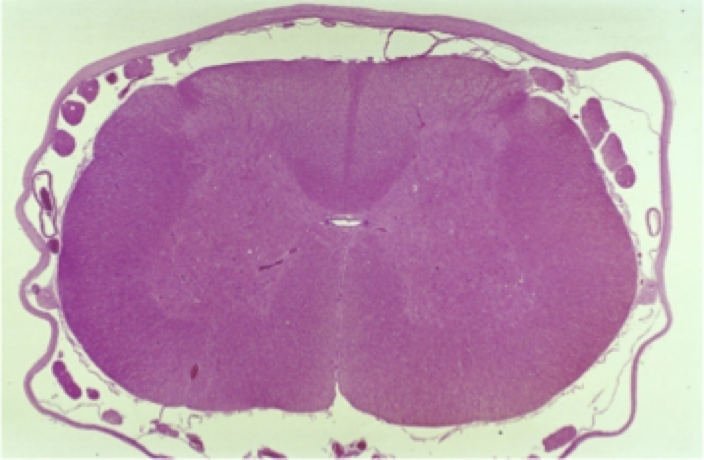

Describe the parenchyma of the spinal cord… where are gray matter and white matter in relation to each other?

White matter → on the OUTSIDE

Gray matter → on the INSIDE

Has a butterfly shape; each side communicate with each other via the gray commissure (surrounds central canal of spine)

Has a dorsal horn → responsible for SENSORY, and a ventral horn → responsible for MOTOR

What can be seen at the center of a transverse histological section of the spine?

The central canal

Lined with EPENDYMAL cells and FILLED WITH CSF